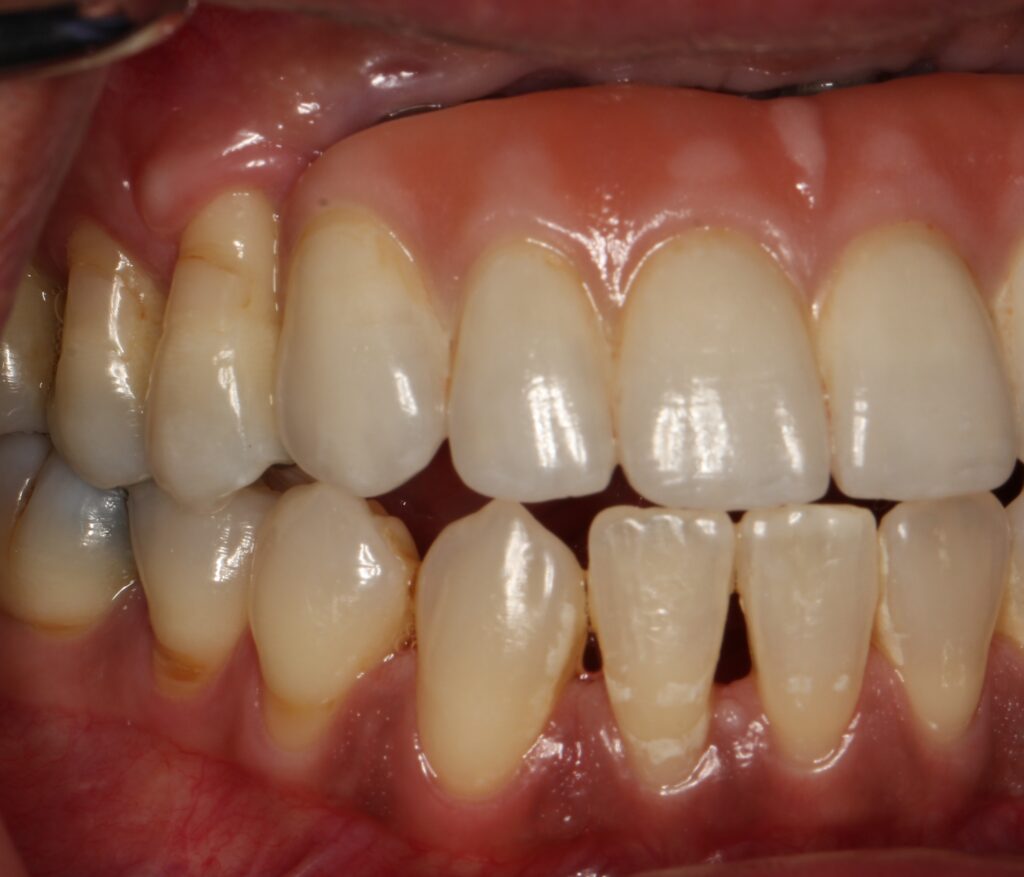

A selection of partial arch fixed implant bridge patients